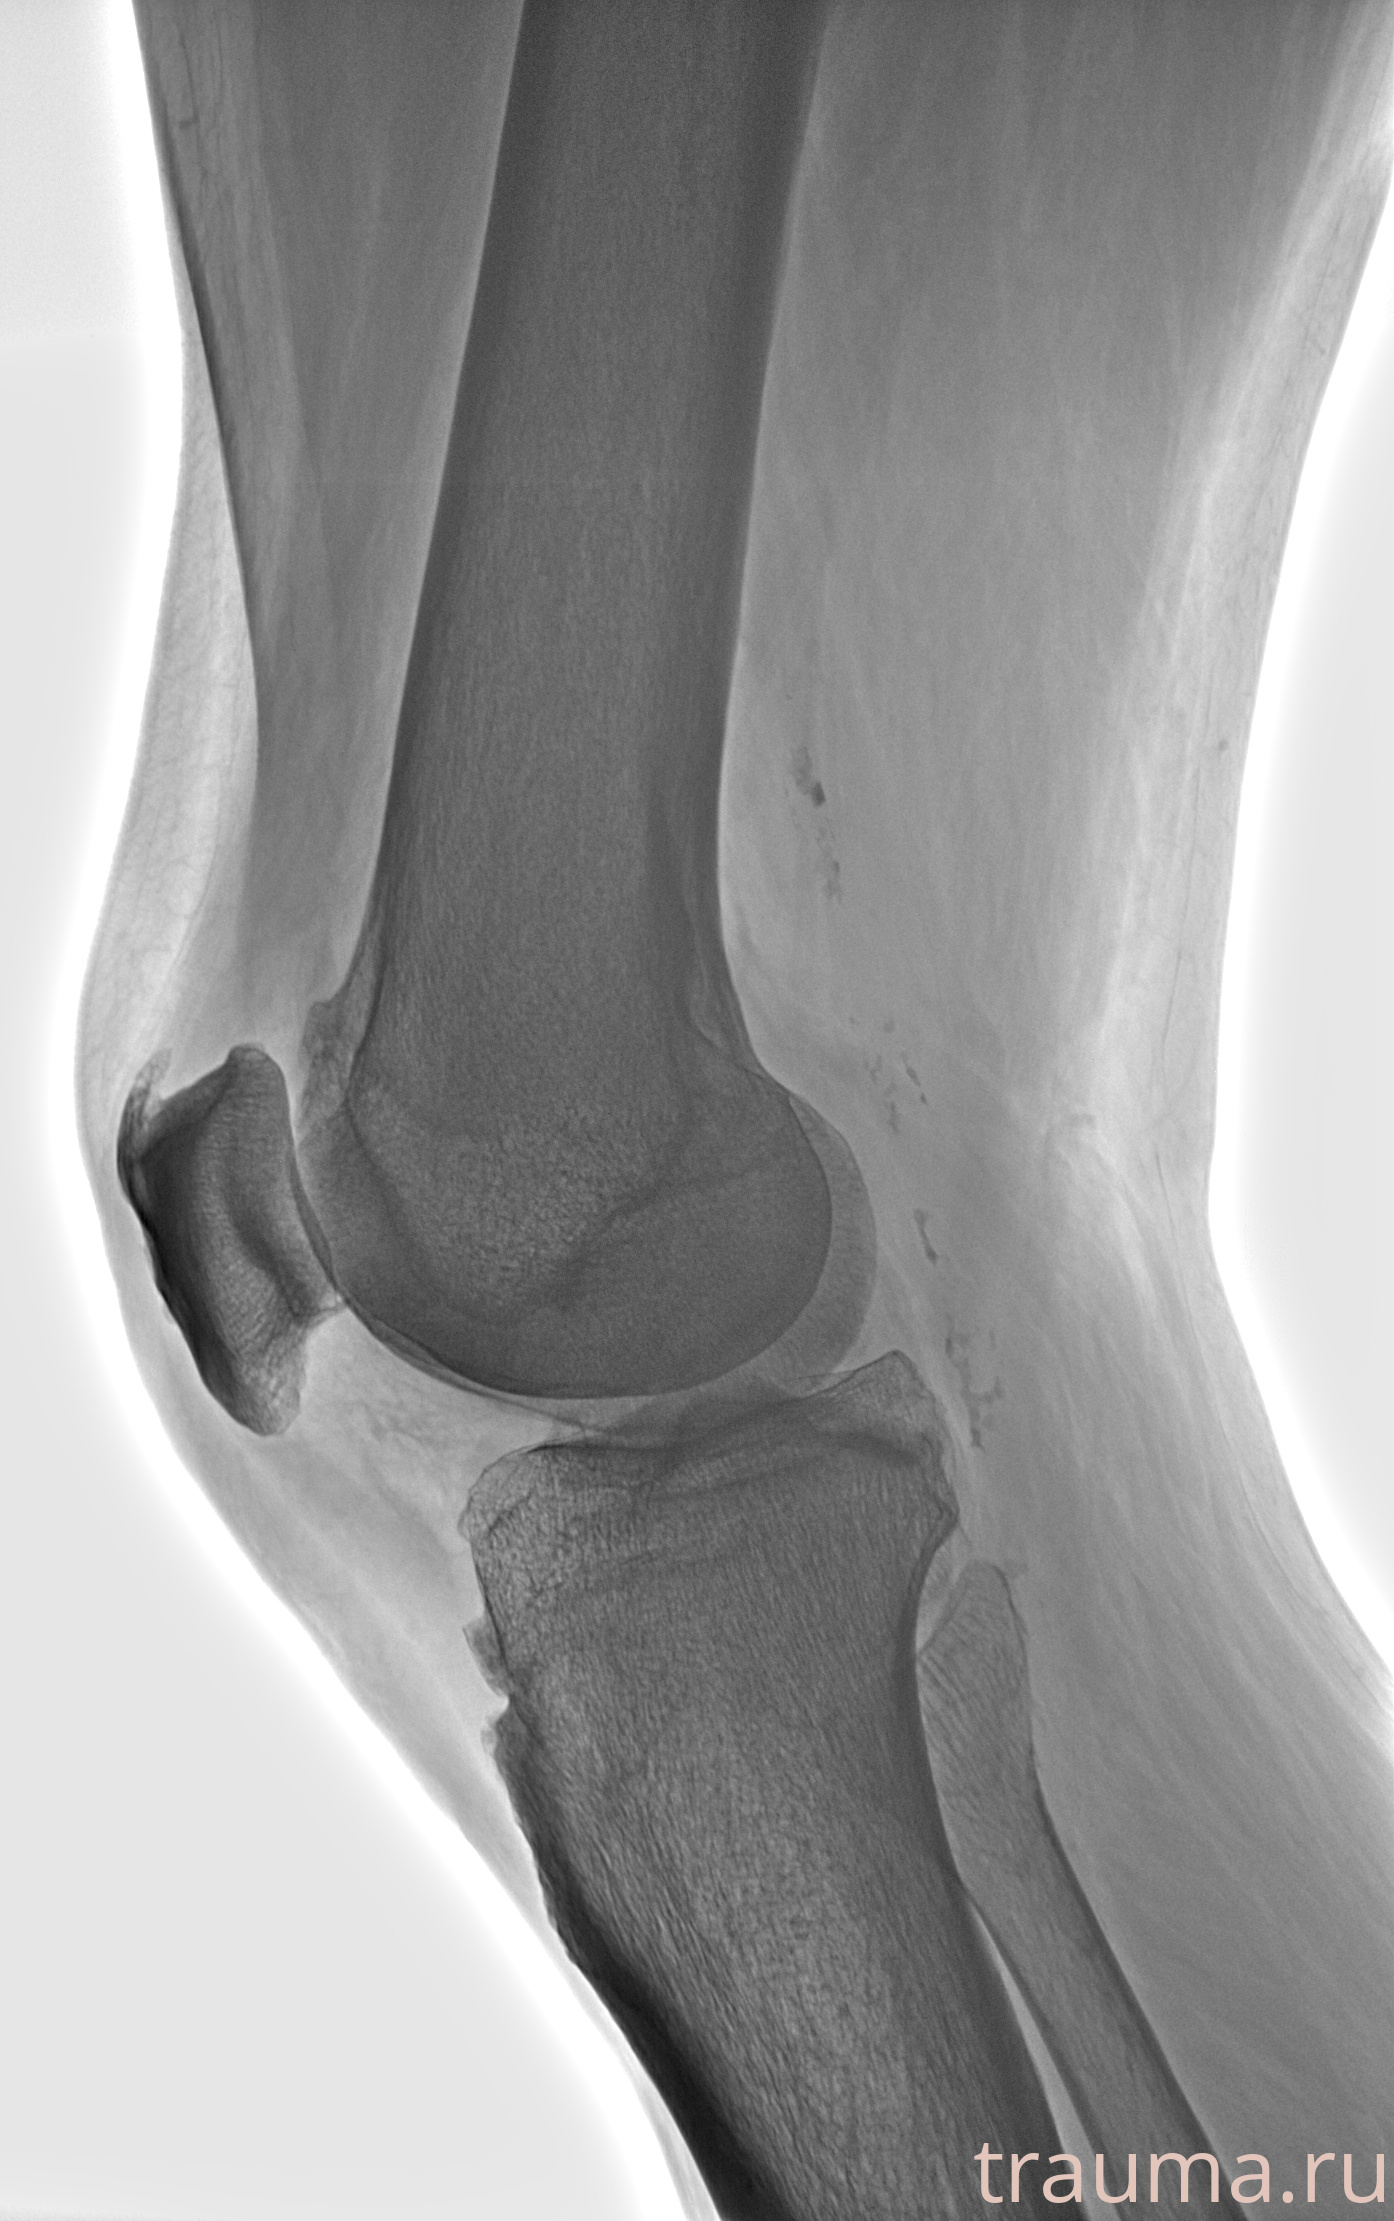

Рентгенограммы

Рентген на дому: по вашему адресу приезжает врач-рентгенолог, травматолог-ортопед с мобильным рентгеновским аппаратом, проводит диагностику травмы или заболевания, делает необходимые рентгенограммы, дает рекомендации по дальнейшему лечению. Получить качественные снимки в домашних условиях возможно благодаря уникальной методике, разработанной МосРентген Центром для института  Склифосовского